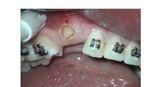

- Afta-Herpes